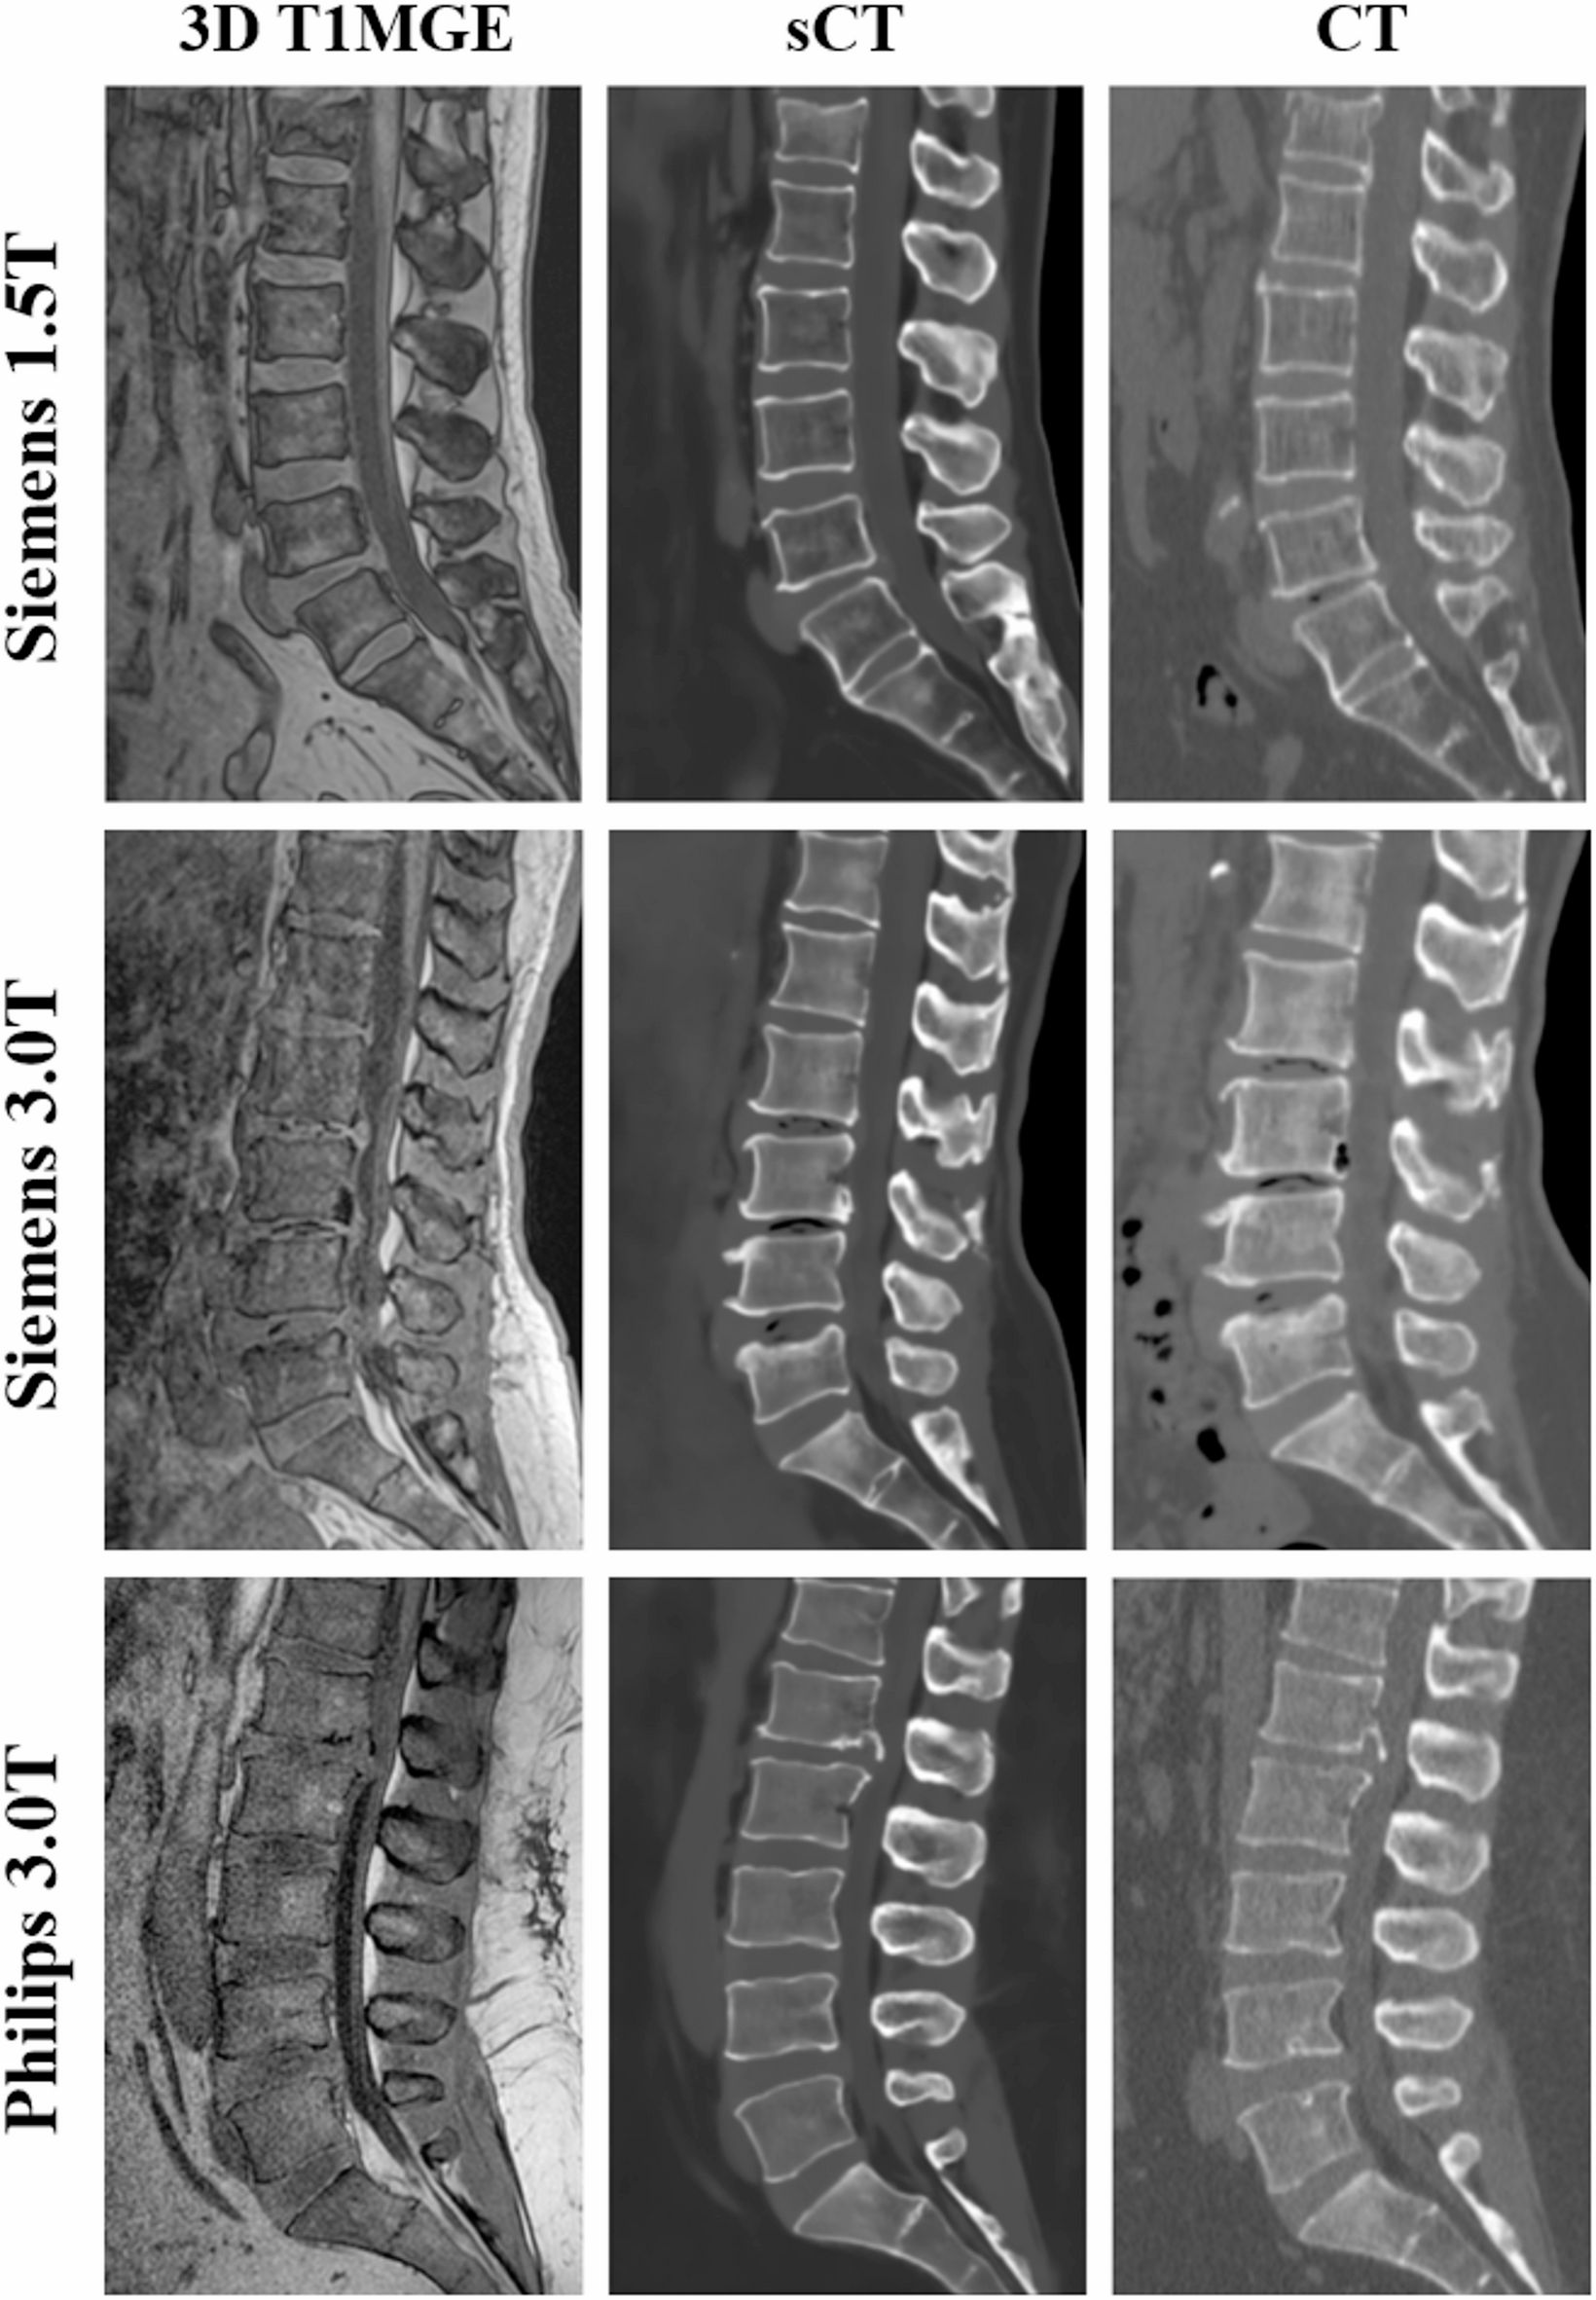

CT는 뼈·출혈, MRI는 신경·근육을 잘 보는 비교 이미지

• 척추·디스크·근육·관절